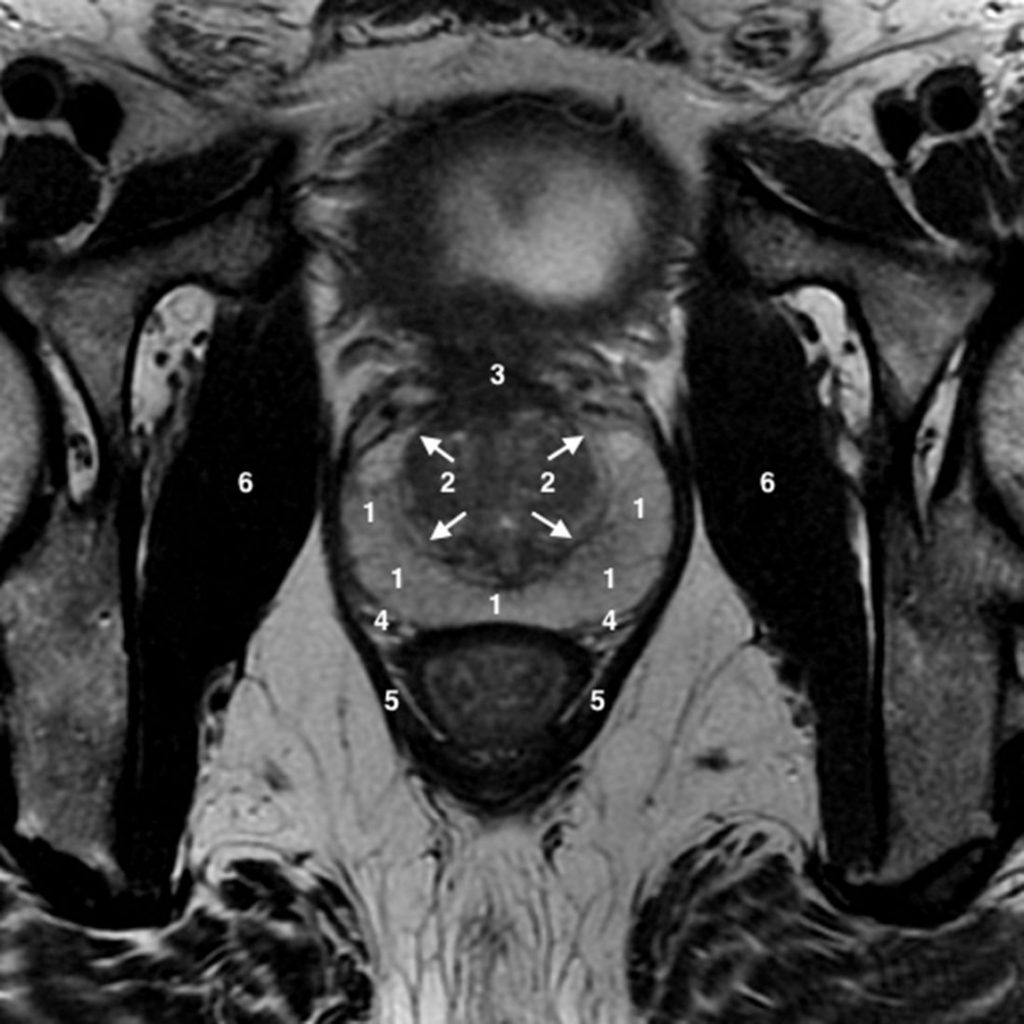

Fig. 19.11. IRM de la prostate : coupe transversale en pondération T2 passant par la partie moyenne de la glande.

1. Zone périphérique. 2. Zone de transition adénomateuse, capsule chirurgicale (flèches blanches). 3. Stroma fibromusculaire. 4. Capsule prostatique. 5. Muscle élévateur de l’anus. 6. Muscles obturateurs internes.

Source : CERF, CNEBMN, 2022.